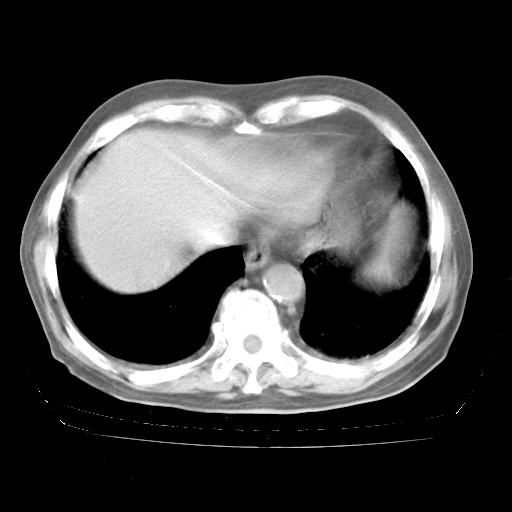

今天部分检查

轻微咳嗽,无痰,(体温正常时)R20次/分,P75次/分,双肺底、腋下可闻及少量捻发音。下肢轻度浮肿。

血常规:白细胞9.11×109/L,N0.92,L5.64,血小板39.2×109/L,HB148g/L,ESR2mm/H。

尿常规:潜血+

血生化:总蛋白69.71g/L,白蛋白38.40g/L,球蛋白31.31g/L,CRP27.9mg/L,尿素氮11.98mmol/L,肌酐106μmol/L,乳酸脱氢酶1099 U/L,肌酸激酶108U/L,CK-MB 61U/L。

腹部B超:胆囊壁增厚,肝、胆、胰、脾、肾无异常,肠系膜淋巴结、腹膜后淋巴结无增大。

ECG:右心室增大

心脏超声检查:无右心室增大。

增加治疗:异烟肼、利福平、乙胺丁醇,静滴左氧氟沙星、参麦注射液。甲强龙从80mg暂减为40mg。

强的松3月1日改为10mg qd,4月1日改为10mg qod。3月份以前的减量过程和环磷酰胺疗程需等明天查看记录(我岳父自己做的记录在他家里)。